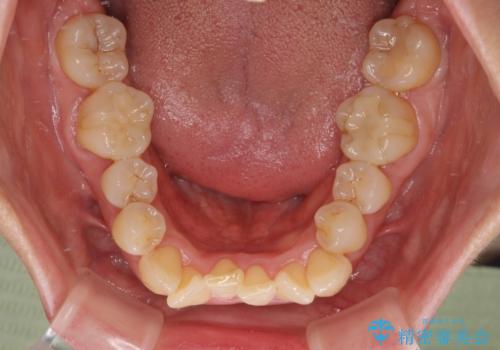

- 上下前歯のデコボコを気にして来院された患者様です。

デコボコは顕著であるものの、口元の突出感は強くないため、非抜歯にて矯正治療を行うこととしました。

元々の叢生と歯肉退縮傾向になる歯肉であったため、ブラックトライアングルが目立つことが想定されました。

治療過程でブラックトライアングル改善のため、IPR(歯と歯の間を削る)を活用しました。